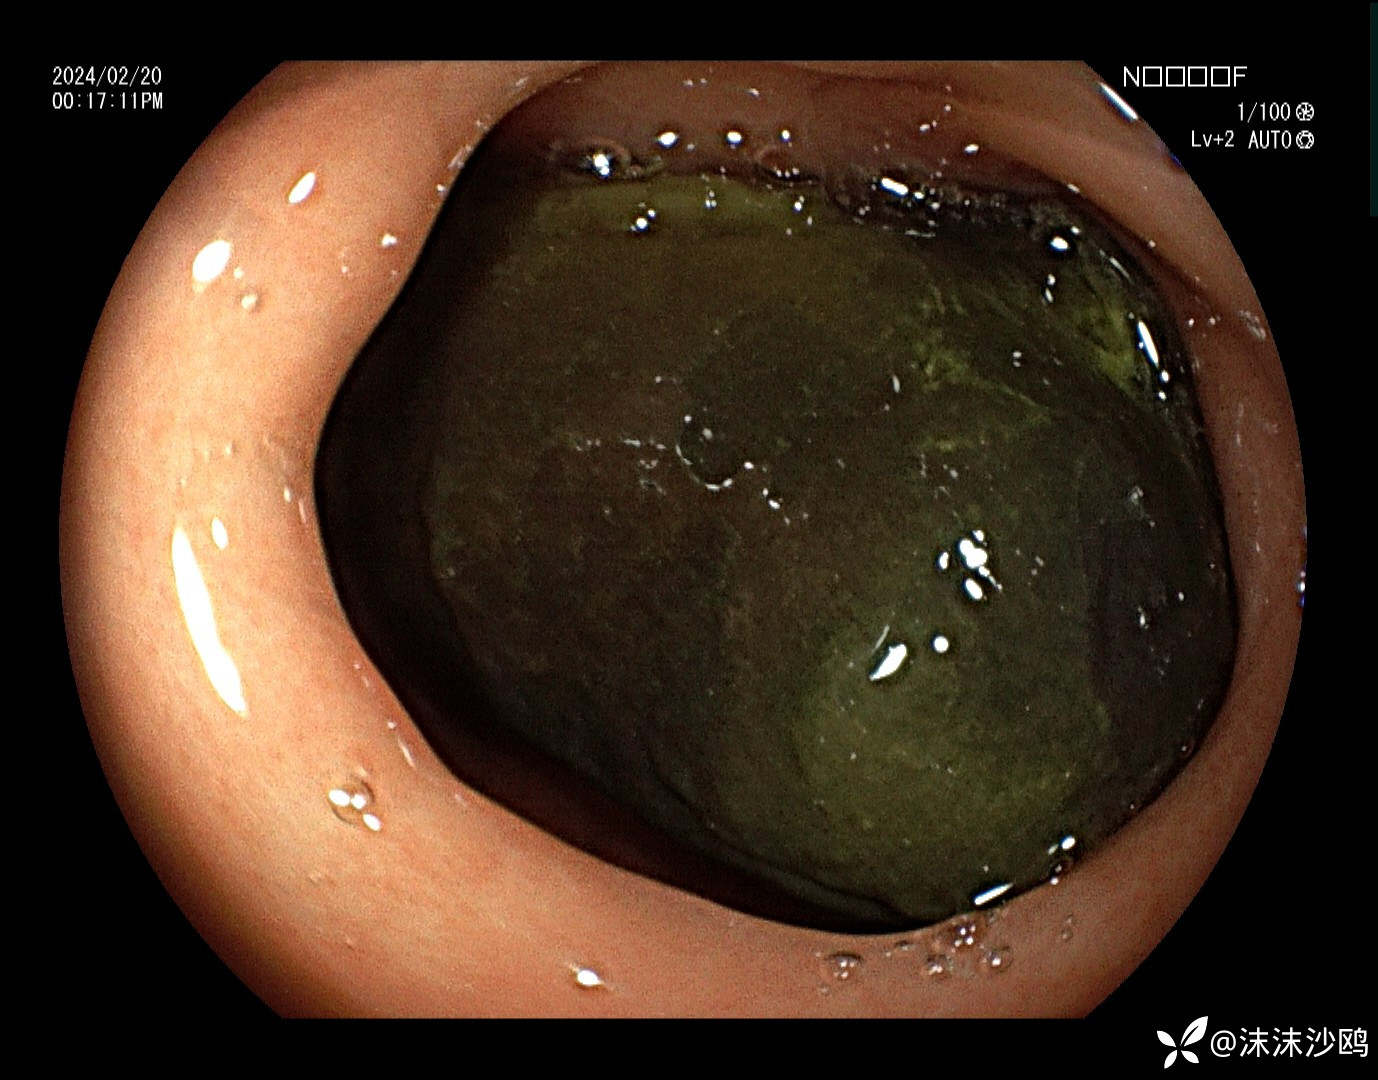

中年男子,腹痛就诊,行普通肠镜检查。胃腔内见大量胃液潴留,吸引了三四百毫升。进到幽门有了发现。

巨大异物嵌顿在球部,考虑胃石导致梗阻。询问病史,就是吃了几个车厘子,没有吃柿子或者山楂之类的。